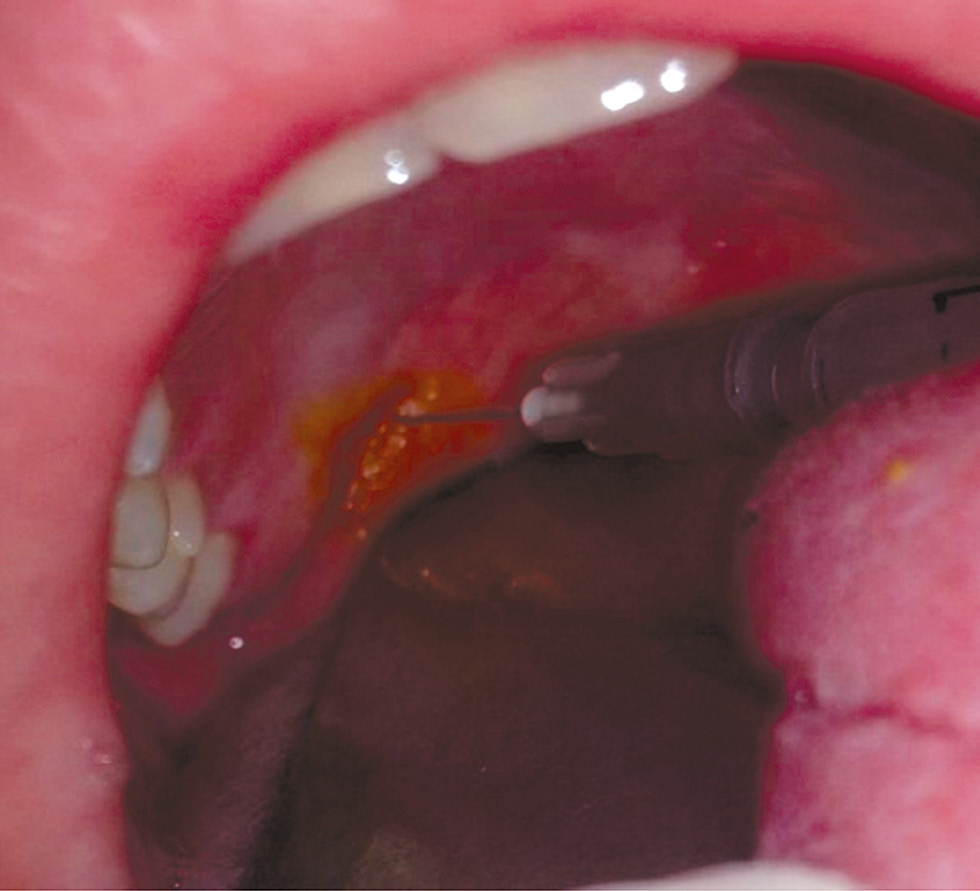

С целью снизить болезненное влияние тампонады носа как локально, так и на весь организм в целом, было принято решение воспользоваться инфильтрационной анестезией носа из трёх точек по Вайсблату, которую выполняли перед экстубацией трахеи.

Техника выполнения инфильтрационной анестезии носа: одна точка укола находится на переносице, откуда игла продвигается с обеих сторон носа косо сверху вниз – изнутри наружу (в медиально-дистальном направлении); две другие точки находятся по обеим сторонам носа на уровне нижней его границы, откуда сначала продвигают иглу в направлении снизу вверх, порционно выпуская местный анестетик, а затем, не вынимая иглы из тканей, направляют её снаружи внутрь параллельно границе носа (рис. 8). Местный анестетик – раствор ропивакаина 0,75% из расчёта V (мл) = возраст в годах/5.

Рис. 8. Инфильтрационная анестезия носа по Вайсблату из трёх точек / Fig. 8. Infiltration anesthesia of the nose by Weissblatt from three points